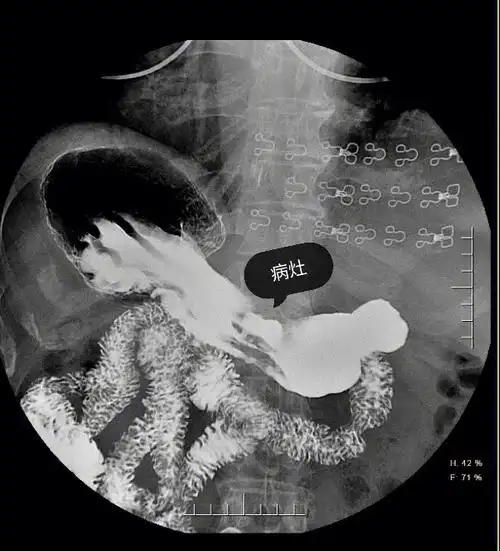

消化道轮廓的改变 龛影(niche)是指钡剂涂布的轮廓有局限性外突的

胃体与胃窦交界区胃小弯侧可见一不规则龛影,位于胃轮廓之内,周围见

可以根据胃的大体形态了解胃的蠕动及是否革袋胃,同时根据龛影和黏膜

胃溃疡(胃小弯侧卫考在线钡剂向腔外突出,形成乳头状龛影.